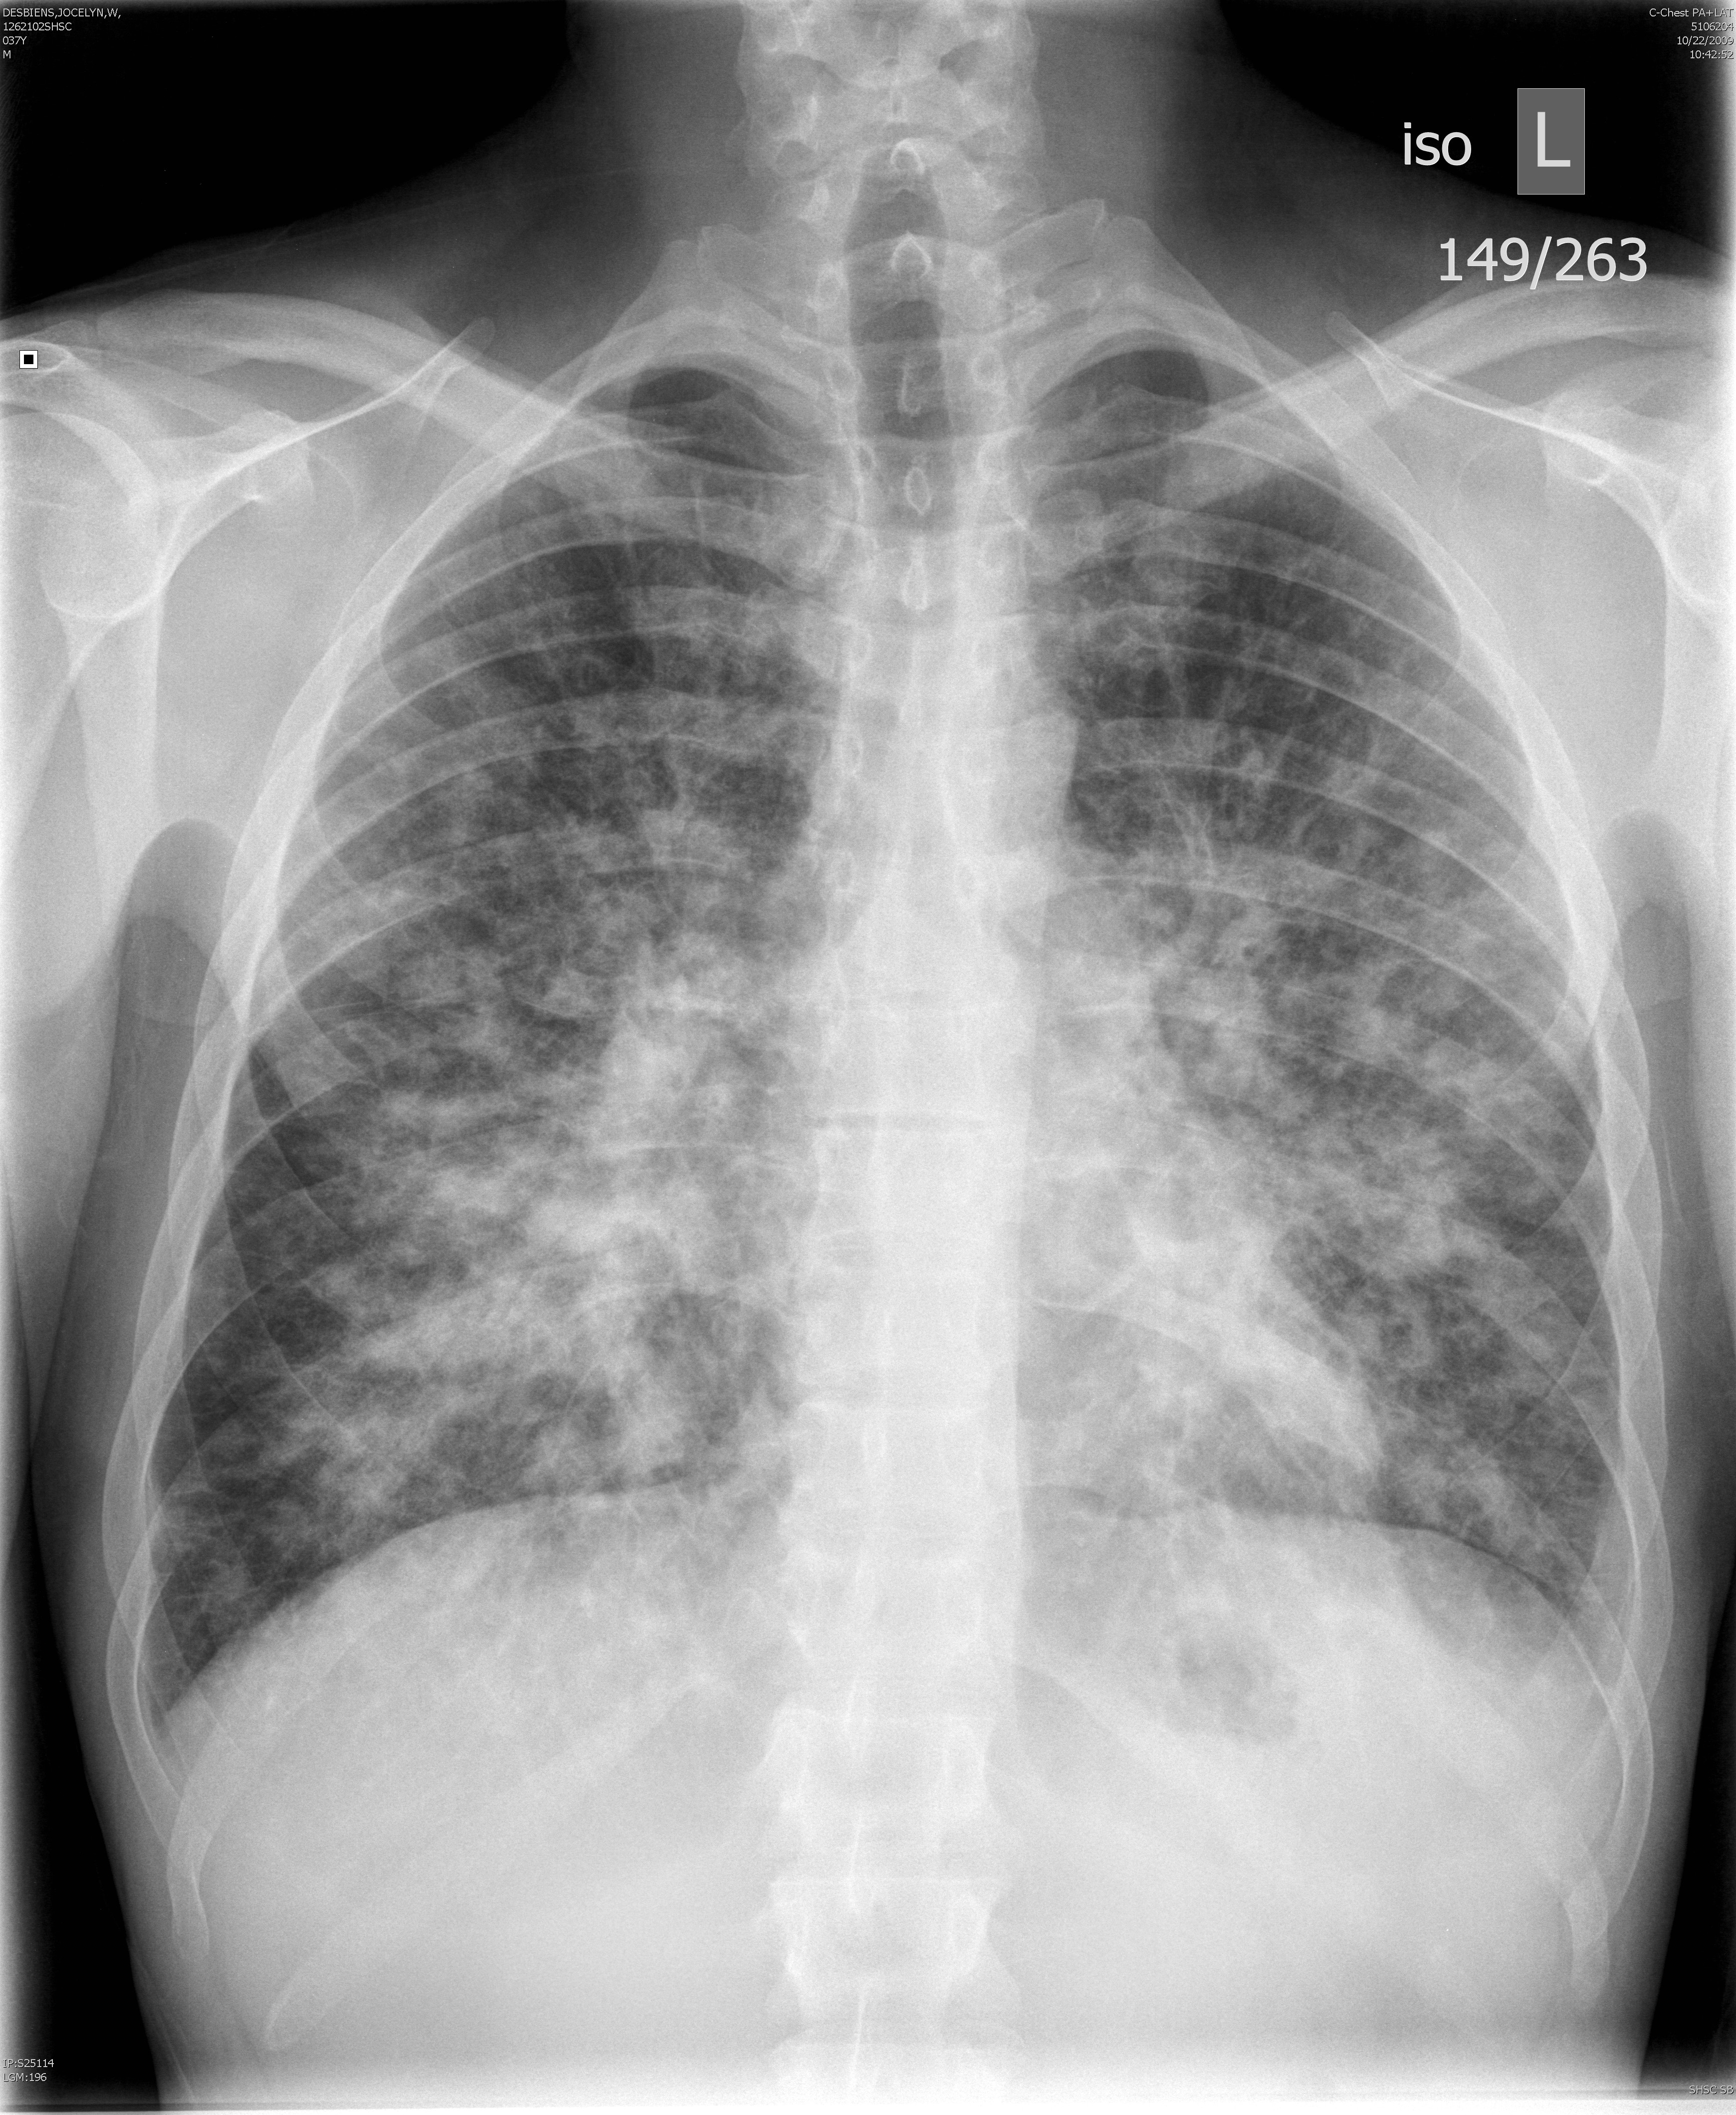

Рентгеновские снимки опухоли Панкоста